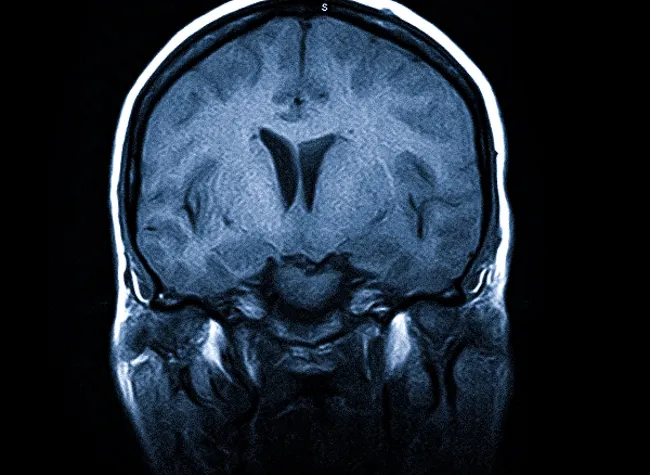

МРТ головного мозга. Т1-взвешенное обследование с контрастом. Шваннома с компрессией четвёртого желудочка.